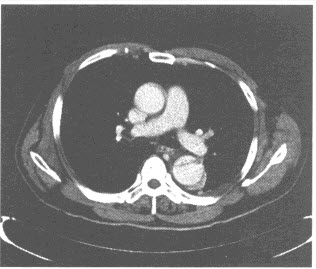

患者,男,25岁。近几年出现吞咽梗阻感,偶出现胸骨后疼痛。行食管吞钡检查如图。

A:病因是食管神经肌肉运动功能障碍,下段食管括约肌呈失弛缓状态而导致食管张力减退、蠕动消失及食管扩张

E:典型的X线表现为食管狭窄并其上段极度扩张